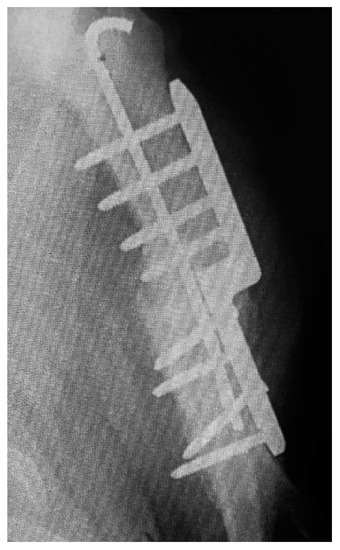

Clinical examinations were also performed at 2, 6, 8, 12, and 14 weeks after surgery. Radiographs of the elbows were taken pre- and post-operative at 6 and 12 weeks (Figure 2 and Figure 3). The owners were asked to assess the dog using a telephone questionnaire (Canine Brief Pain Inventory).

Figure 3. Post-operative view of callus formation.